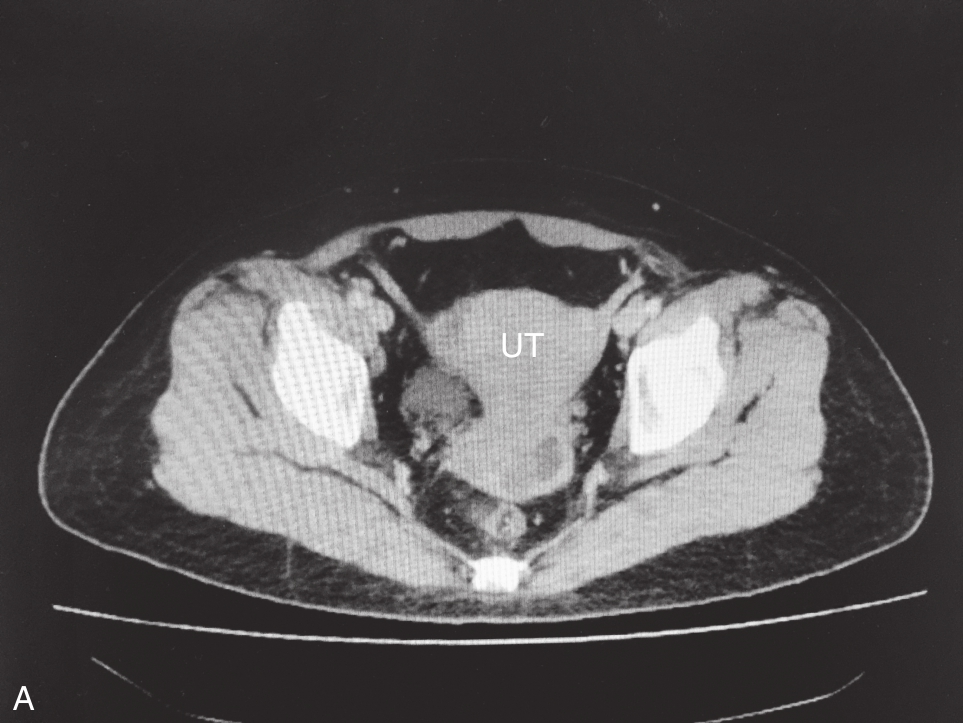

右卵巢上囊肿的经静脉超声造影见图3-12-4及ER 3-12-2。注入造影剂14s,囊肿囊壁开始出现增强(图3-12-4A箭头所示),晚于子宫肌层增强;注入造影剂后18s,囊壁呈较均匀等增强(图3-12-4B箭头所示);注入造影剂后22s,囊肿内始终未见造影剂进入(图3-12-4C箭头所示)。

图3-12-4 右卵巢上囊肿经静脉超声造影声像图

A.注入造影剂后14s;B.注入造影剂后18s;C.注入造影剂后22s。C:囊肿。

右卵巢上囊性占位病灶,经静脉超声造影有如下特点:①囊肿囊壁增强呈“慢进”;②囊壁呈较均匀等增强,其内始终未见造影剂进入。综上,造影表现为囊壁呈“慢进”的均匀等增强,囊内始终未见造影剂灌注;均提示囊肿良性可能。随访观察发现该囊肿自行消失。